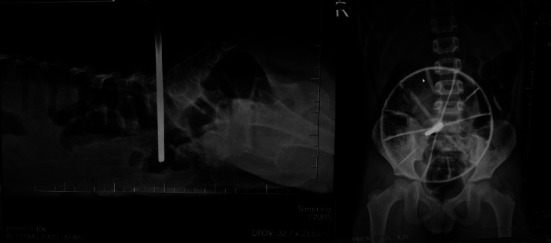

Traumatic penetrating injuries to the back are uncommon in children. This type of injury presents many considerations for airway management to the anesthesiologist, including having to secure the airway in a prone position. Although there have been several reports about intubation in the prone position for adult patients in emergency conditions, such studies on pediatric patients are rare. We present the case of a male child with an impaled steel shaft connected to a toy car wheel in his lower back, requiring an emergent operation under general anesthesia. Due to resource limitations, the patient was intubated using an adult-sized video laryngoscope in the prone position. The patient remained stable during the operation and was discharged without complications. A postoperative discussion was held later to review the case and gain insights from the rest of the anesthesiology team. Prone intubation in pediatric patients can be safely accomplished using various techniques, depending on the urgency of the need, the availability of resources, and the knowledge and skills of the provider. The authors hope that their colleagues can learn from sharing this experience.